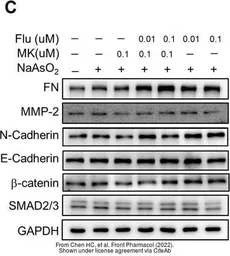

The data was published in the 2022 in Front Pharmacol. PMID: 35517780

The data was published in the 2022 in Front Pharmacol. PMID: 35517780

The data was published in the 2022 in Front Pharmacol. PMID: 35517780